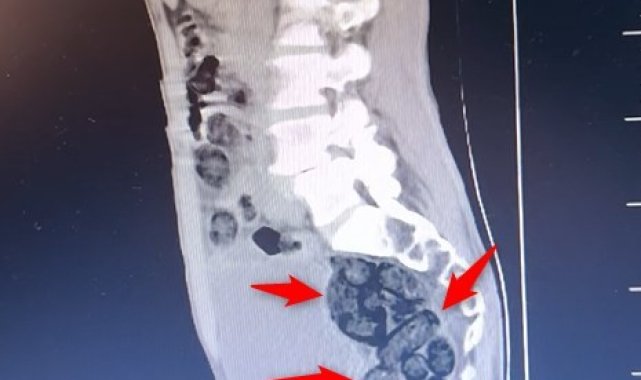

Batman'da durdurulan otobüsteki yabancı şahsın midesinden 64 parça uyuşturucu maddesi metamfetamin çıktı.Batman İl Emniyet Müdürlüğü Narkotik Suçlarla Mücadele Şube Müdürlüğü ekiplerince Batman Cumhuriyet Başsavcılığı koordinesinde yürütülen çalışmalar kapsamında Batman girişinde durdurulan otobüste arama yapıldı.Durumundan şüphelenilen yabancı uyruklu bir yolcu üzerinde arama yapıldı. Yapılan incelemeler sonucunda yabancı uyruklu şahsın midesinde 64 Parça halinde toplam 472 gram uyuşturucu maddesi metamfetamin olduğu belirlendi.Gözaltına alınan şahsın midesindeki uyuşturucu madde çıkartıldı. Emniyetteki işlemlerinin ardından adliye sevk edilen şahıs, çıkarıldığı mahkemece tutuklanarak cezaevine gönderildi.

Batman'da yabancı uyruklu bir şahsın midesinden 64 parça uyuşturucu çıktı

Batman'da durdurulan otobüsteki yabancı şahsın midesinden 64 parça uyuşturucu maddesi metamfetamin çıktı.